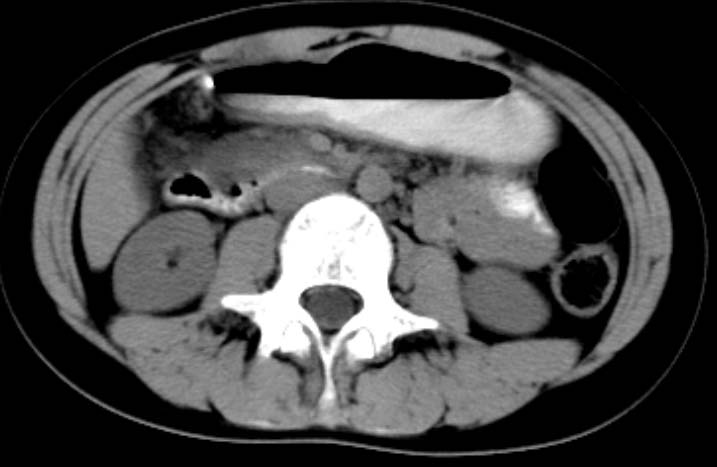

女,14岁。腹痛3天。腹部触诊未触及包块。碘剂阳性未增强。求助战友。。。。。。。。。。。

胰头部增大,周围模糊,有渗出,胰腺炎可能性大,建议结合化验检查;左侧输尿管上段略扩张.

1)急性胰腺炎。2)肝右叶后上段肝内胆管结石。3)左侧输尿管上段扩张,原因待查。

是不是胰腺炎结合几项化验指标确诊不是问题,我觉着下腹部及盆腔应观察一下。

病灶应在胰头下区,不一定是胰头,结合周边低密度水肿,是否可能为十二指肠(xi)室炎症或其它炎症。

胰周无明显渗出,吉氏筋膜未见增厚。血尿试验室检查不支持。排除胰腺炎。